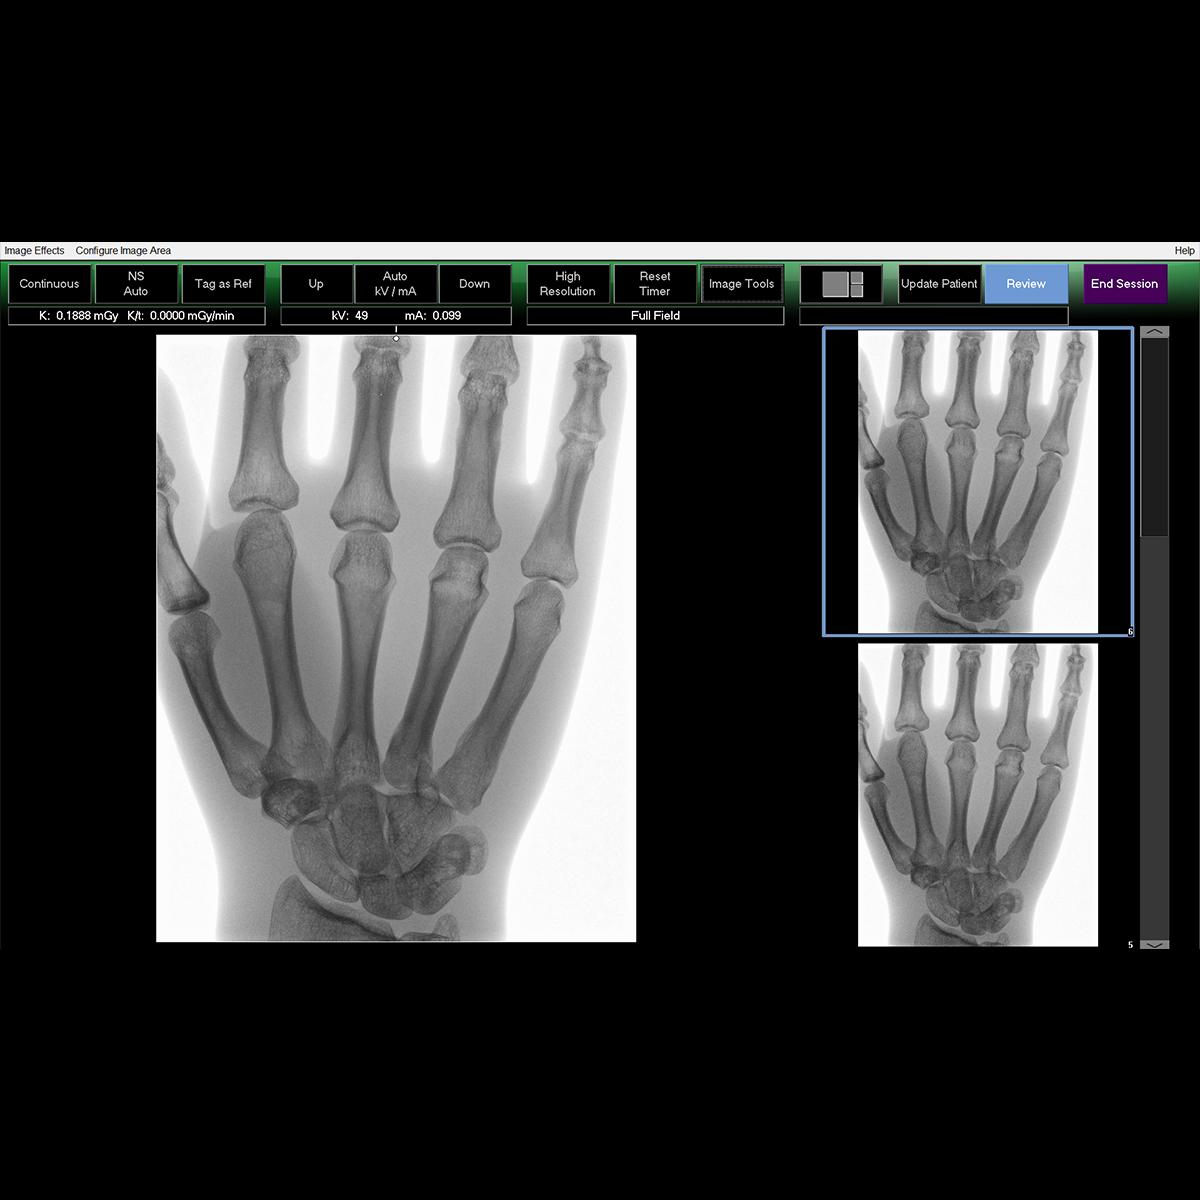

Clinical Images

Image quality to rival standard X-ray

- Image processing algorithms deliver superb distortion-free image quality.

- System allows larger anatomy imaging with dose optimization.

- Automatic imaging with dose optimization for all extremity imaging.

- HD touch-screen monitor with finger touch rotation, easy zoom, color directionality and improved searchability.

- MegaView™ Image capability to view a 50% larger image.